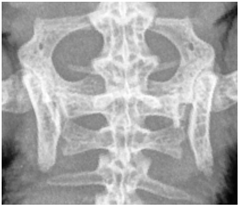

![]() | Cruciate vertebrae, 1st–3rd caudal vertebrae: identifiability of the individual vertebral bodies:assessability of the architecture and external contour of the vertebral bodies, delineability of the vertebrae from each other and from the surrounding area. |